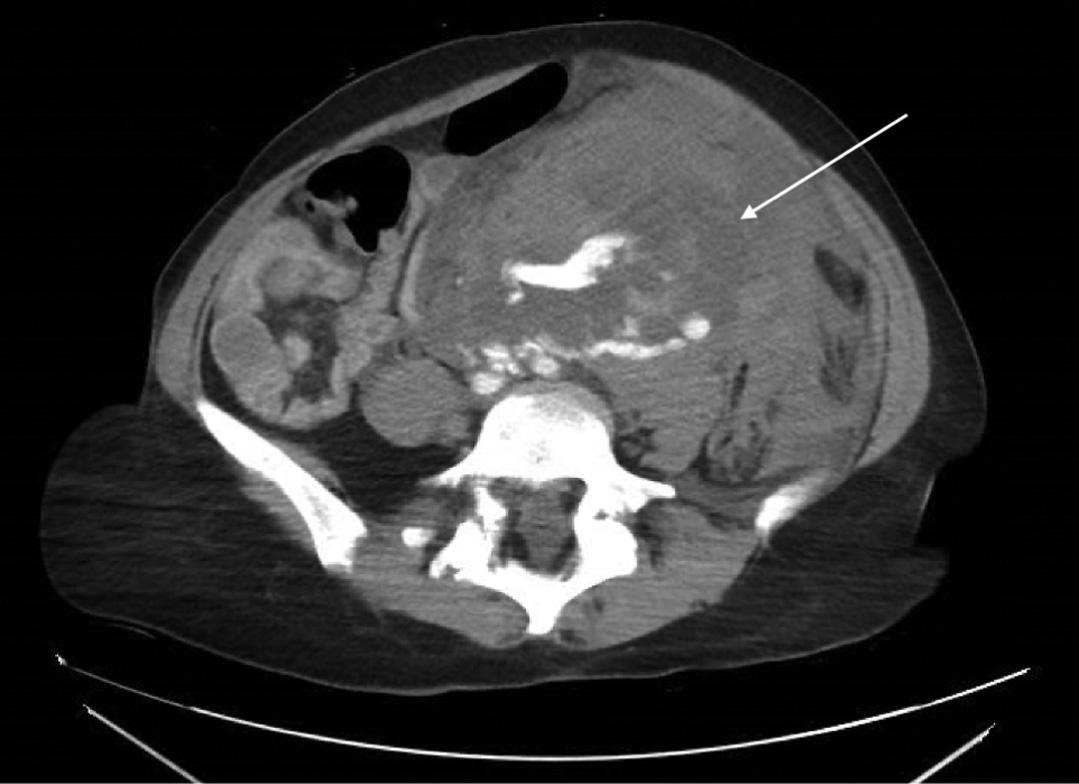

Emergentcomputedtomographyoftheabdomenand pelvisrevealedalargeleftretroperitonealandperitoneal hematomasecondarytoleftRAArupture,aswellasconcern fordevelopingsplenicinfarctsintheleftlowerrenalpole (Image).Thepatientwastakenemergentlytotheoperating room(OR)forexploratorylaparotomywithintwohoursof EDarrival.Sheunderwentsuprarenalcross-clampingwith repairoftheleftrenalarteryandligationofrenalvessels.She returnedtotheORtwodayslaterforleftnephrectomyand abdominalclosure.Shewasextubatedandtransferredtothe floor.Shewasdischargedhometwodayslaterin goodcondition.